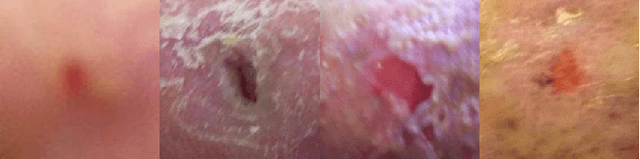

Abstract:Diabetic foot ulcer classification systems use the presence of wound infection (bacteria present within the wound) and ischaemia (restricted blood supply) as vital clinical indicators for treatment and prediction of wound healing. Studies investigating the use of automated computerised methods of classifying infection and ischaemia within diabetic foot wounds are limited due to a paucity of publicly available datasets and severe data imbalance in those few that exist. The Diabetic Foot Ulcer Challenge 2021 provided participants with a more substantial dataset comprising a total of 15,683 diabetic foot ulcer patches, with 5,955 used for training, 5,734 used for testing and an additional 3,994 unlabelled patches to promote the development of semi-supervised and weakly-supervised deep learning techniques. This paper provides an evaluation of the methods used in the Diabetic Foot Ulcer Challenge 2021, and summarises the results obtained from each network. The best performing network was an ensemble of the results of the top 3 models, with a macro-average F1-score of 0.6307.

Abstract:This paper introduces the Diabetic Foot Ulcers dataset (DFUC2021) for analysis of pathology, focusing on infection and ischaemia. We describe the data preparation of DFUC2021 for ground truth annotation, data curation and data analysis. The final release of DFUC2021 consists of 15,683 DFU patches, with 5,955 training, 5,734 for testing and 3,994 unlabeled DFU patches. The ground truth labels are four classes, i.e. control, infection, ischaemia and both conditions. We curate the dataset using image hashing techniques and analyse the separability using UMAP projection. We benchmark the performance of five key backbones of deep learning, i.e. VGG16, ResNet101, InceptionV3, DenseNet121 and EfficientNet on DFUC2021. We report the optimised results of these key backbones with different strategies. Based on our observations, we conclude that EfficientNetB0 with data augmentation and transfer learning provided the best results for multi-class (4-class) classification with macro-average Precision, Recall and F1-score of 0.57, 0.62 and 0.55, respectively. In ischaemia and infection recognition, when trained on one-versus-all, EfficientNetB0 achieved comparable results with the state of the art. Finally, we interpret the results with statistical analysis and Grad-CAM visualisation.